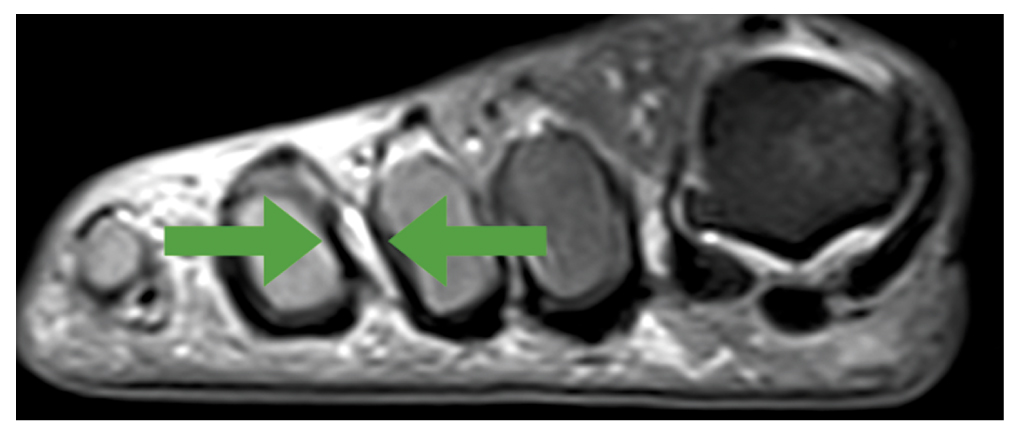

Протокол МРТ включал получение изображений в трёх плоскостях: прямая коронарная, прямая сагиттальная и аксиальная. Были выполнены серии МРТ, взвешенных по Т1-ВИ и Т2-ВИ, в трёх проекциях с жироподавлением (рис. 1, 2).

Рис. 2. Гипоинтенсивный сигнал при сравнении с мышцами на Т1-ВИ непосредственно в области III межпальцевого промежутка.